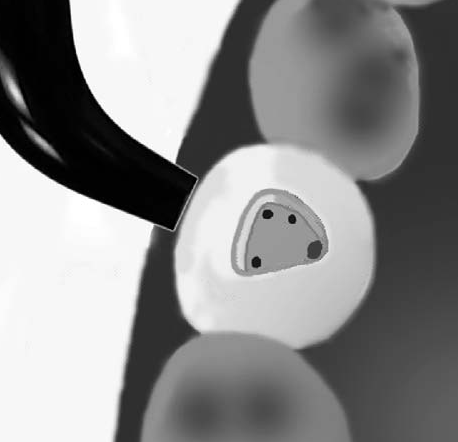

Como método para ubicar los orificios de entrada de los conductos solemos utilizar la transiluminación dentaria.

El conducto y el orificio es esencialmente un agujero en la raíz, la transmisión de luz  muestra al orificio de entrada del conducto como una mancha oscura en un fondo brillante. Ver imagen izquierda superior, la siguiente imagen es el resultado de utilizar una cámara intraoral, con 10 aumentos (X10)

En la imagen derecha se observa el dispositivo de transiluminación dentaria

Observe en la imagen superior la dentina secundaria de color blanca que obstruye la entrada de los conductos. Imagen X10 cámara intraoral.

Tres conductos en piso de cámara pulpar, el conducto distal se encuentra ensanchado en sentido buco-lingual, debe sospechar la existencia de dos conductos que comparten el orificio de entrada. Cámara intraoral X10 aumentos.

DS: dentina secundaria de color más claro. Cámara intraoral X10 aumentos.